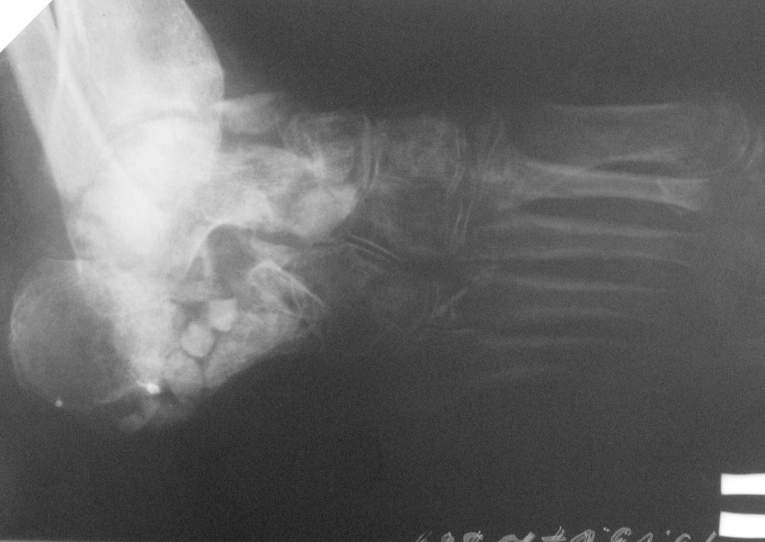

Приветствую. Некоторое время назад я выкладывал случай с остеомиелитом пяточной кости. Ответов я не дождался, но суть в другом.

У этой пациентки проблема была похожа тем, что свищи открывались когда она пыталась вставать на больную ногу. Была произведена санация полости пяточной кости, установлены бусы с ванкоминцином,разрешена нагрузка, пациентка показывалась через месяц, свищи не открывались с момента санации. На данный момент есть только снимки со спейсером, в следующую явку обязательно сфотографирую ногу "живьем". Можно добавить, что при санации пользуем "зеленку" с перекисью для окрашивания мертвых тканей через свищ. Бусинки лучше делать маленьких размеров - легче укладывать(особенно в костную полость), на эти грабли я уже наступил:)